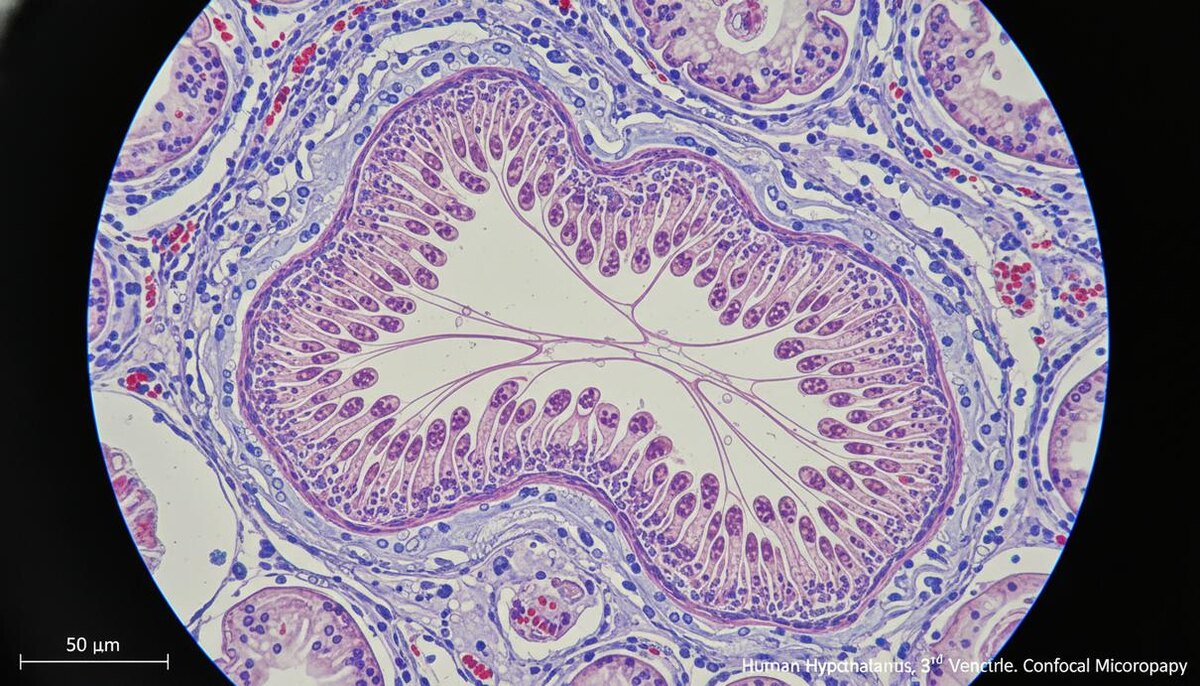

Танициты представляют собой клетки неврального происхождения, расположенные преимущественно в районе третьего желудочка головного мозга. Предыдущие изыскания подтвердили их участие в передаче метаболических сигналов между кровотоком и спинномозговой жидкостью. Эта жидкость окружает головной и спинной мозг, выполняя функцию коммуникационной сети для поддержания внутреннего баланса в организме.